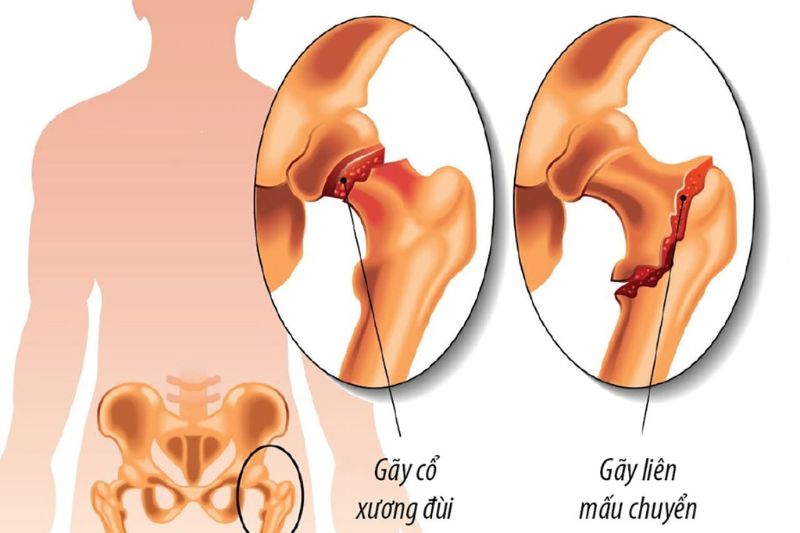

Phẫu thuật thay khớp háng bán phần còn được thực hiện đa số trong trường hợp chấn thương gãy cổ xương đùi hoặc gãy mấu chuyển xương đùi ở người già hoặc những người tổn thương khớp háng thể trạng yếu không thực hiện được phẫu thuật thay khớp háng toàn phần.